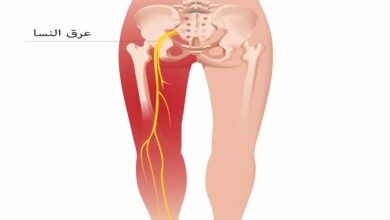

- وأمراض الجهاز العصبي المركزي والمحيطي تسبب في بعض الأحيان الإصابة بالإمساك، منها مرض باركنسون، السكتة الدماغية، وأورام الدماغ والخرف.